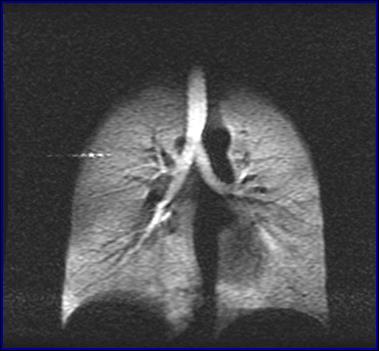

中國科學院武漢物理與數學研究所研究員周欣、中科院院士葉朝輝帶領的科研團隊克服技術難關,研制出具有自主知識產權的人體肺部氣體磁共振成像系統。該系統彌補了傳統磁共振成像不能檢測肺部空腔結構的缺陷,成功“點亮”人體肺部,且能同時獲得肺部氣氣、氣血交換的功能信息,成為肺癌等重大疾病早期科學研究和診斷的新利器。目前,該成果已轉移轉化成立產業化公司,且正在申請醫療器械注冊證。2018年7月在同濟醫院建立了第一個肺部氣體磁共振臨床檢測中心,用于大規模臨床病例獲取工作。

人體肺部氣體磁共振成像系統

左:核心裝置超極化氣體發生器 右:我國首幅人體肺部氣體磁共振成像圖